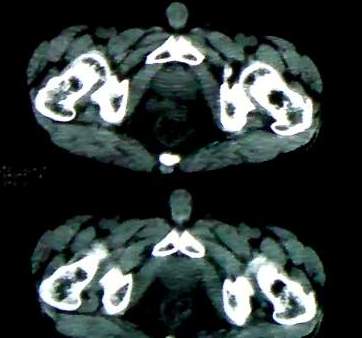

男 60岁,下腹部肿块半年余

前列腺肥大,密度不均。伴盆腔实性肿块。考虑前列腺癌伴盆腔转移。建议增强扫描。

考虑来源于肠道的肿瘤,乙状结肠?询问排便情况

盆腔恶性占位,间质瘤可能性大

乙状结肠间质瘤

盆腔恶性占位,间质瘤可能性大。

考虑盆腔内间质瘤可能性大。

病理结果:肠系膜肉瘤

病灶形态不规则,偏心性裂隙样坏死,支持恶性病变。来源不好定。感谢反馈结果--肠系膜肉瘤。